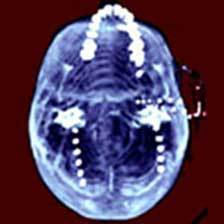

1.脑囊虫病 病例报告:女,13岁,一次外出始突然发作四肢抽搐,牙关紧闭,双眼球固定,唤之不应,持续3~5分钟,伴发热(38℃),急送当地医院诊治。头颅CT检查无明显异常,拟诊“抽搐待查,原发性癫痫?”对症治疗,抽搐及发热症状消失,除记忆力稍减退外,无其余异常。回家后又有类似发作2次,每次发作前均有一过性记忆力减退,继而出现抽搐,伴发热,体温均超过38℃。

避免误诊:脑囊虫病可继发癫痫发作,详细询问病史及查体,部分患者可见皮下、肌肉或眼内小结,病理检查可发现囊虫;血常规及脑脊液检查可见嗜酸性细胞增多;囊虫免疫诊断试验其特异性抗体可为阳性;头颅CT或MRI检查可发现囊虫病灶。

4.脑穿通畸形 病例报告:男,30岁,1岁时右肢体力弱,发作性全身痉挛性抽搐伴尿失禁,智能发育迟缓,曾诊断为大脑发育不全、癫痫,抗癫痫治疗无效,智能障碍逐年明显。

避免误诊:本病又称脑穿通性囊肿,头颅CT检查或MRI检查若发现脑内囊肿性病变,脑室和蛛网膜下腔相通,有助于明确诊断。